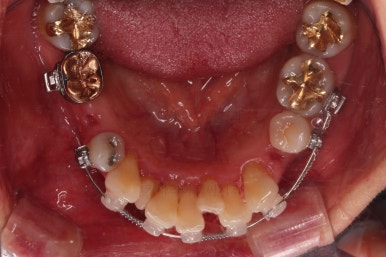

동래임플란트교정 초진 시 입안의 모습입니다.

치열이 전반적으로 삐뚤어져 있는 양상이고요.

아랫니가 윗니보다 더 많이 삐뚤어 있는데요.

비밀은 바로 화살표에 있습니다.

유치 잔존

말그대로 어릴 때 빠져야 할 유치가 남아있다는 뜻인데요.

앞니 사이에 뾰족하게 남아있다 보니 자리만 많이 차지하고 있는 모습이었고 다른 영구치를 더 삐뚤게 만들었어요.

딱히 영구치가 모자라진 않는데 유치가 잔존하는 굉장히 드물고 독특한 상황이었습니다.

당연히 유치는 뽑기로 했고요.